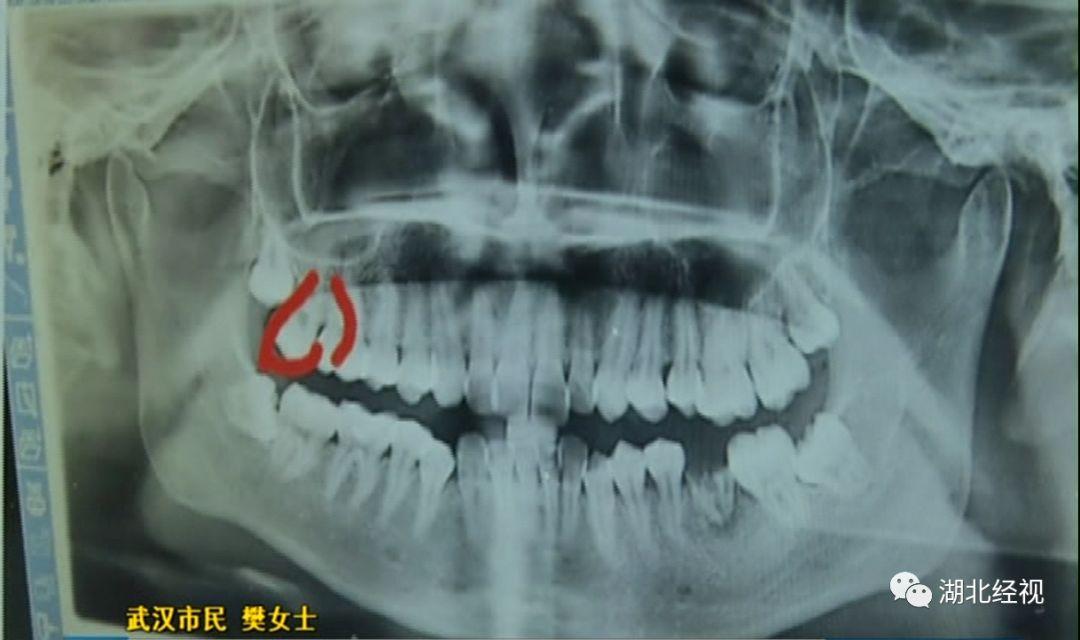

樊女士說,拔牙時上了麻醉,嘴巴里都是麻的也沒有感覺。但回家一個星期后照鏡子,突然發(fā)現(xiàn)自己的一顆好牙沒有了,一顆好牙齒被這樣被拔掉了。

原本是準(zhǔn)備拔掉多余的牙齒,但醫(yī)生卻意外拔掉了一顆好牙,這讓樊女士痛心不已。

記者陪同樊女士找到了武漢第一口腔醫(yī)院,院方醫(yī)務(wù)部門對于錯拔樊女士好牙的投訴并不否認,并表示已對醫(yī)生進行了批評。